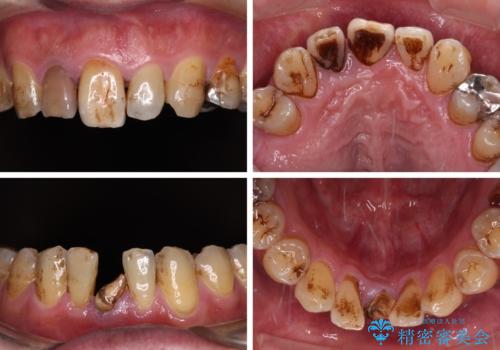

放置した歯列 矯正治療とインプラント治療で劇的に改善

- むし歯治療途中で放置された歯が多く、スペースができたり歯が寄って来たりしているのを気にして来院された患者様です。

矯正治療を行いながら、欠損部はインプラントによる補綴治療を希望されたため、補助装置を用いたワイヤー矯正によりスペースを確保しながら歯列を整え、適宜インプラントを埋入していくこととしました。

上顎前歯もインプラントを希望していらっしゃいましたが、両隣の歯根が近接しており、インプラントは困難と判断したためオールセラミックブリッジによる補綴治療を前提として治療を開始することとしました。